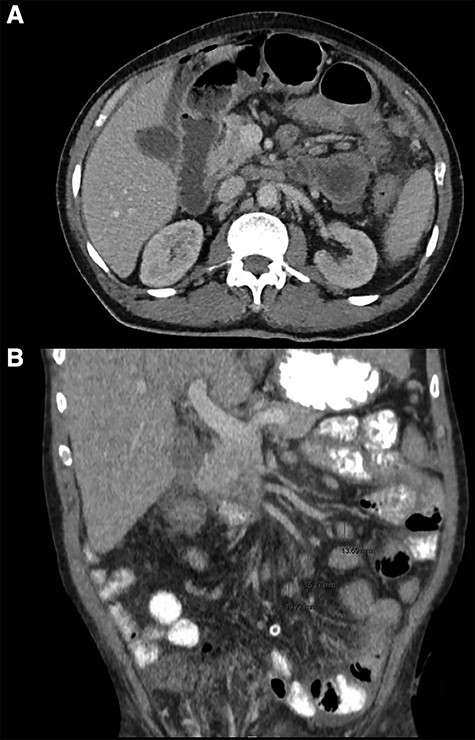

CT thorax abdomen, axial (A) and coronal (B) images. (A) Intra-abdominal free air and fluid, perihepatic, mesenteric and pelvic. (B) Mesenterial lymphadenopathy.

Computed tomography (CT)-imaging of the thorax and abdomen revealed intra-abdominal air and free fluid, suggestive of perforation of an unknown origin (Fig. 1A). Additionally, there were signs of pulmonary sarcoidosis and hilar and mesenteric lymphadenopathy.